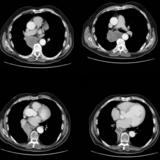

Mass  RLL collapse 5 CT

Date: 03/02/2006

Views: 3889